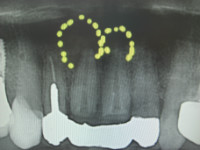

今日のオペは上顎左右1番の歯根端切除と骨補填です。

この部位の根尖には歯冠大の歯根嚢胞があり、ずっと根管治療を行ってきたのですが、根尖からの排膿が消失せずなかなか良くならなかった為に、歯根嚢胞と感染した根尖部を根こそぎ除去してしまう歯根端切除術,及び骨補填する術式を選択することになった次第です。